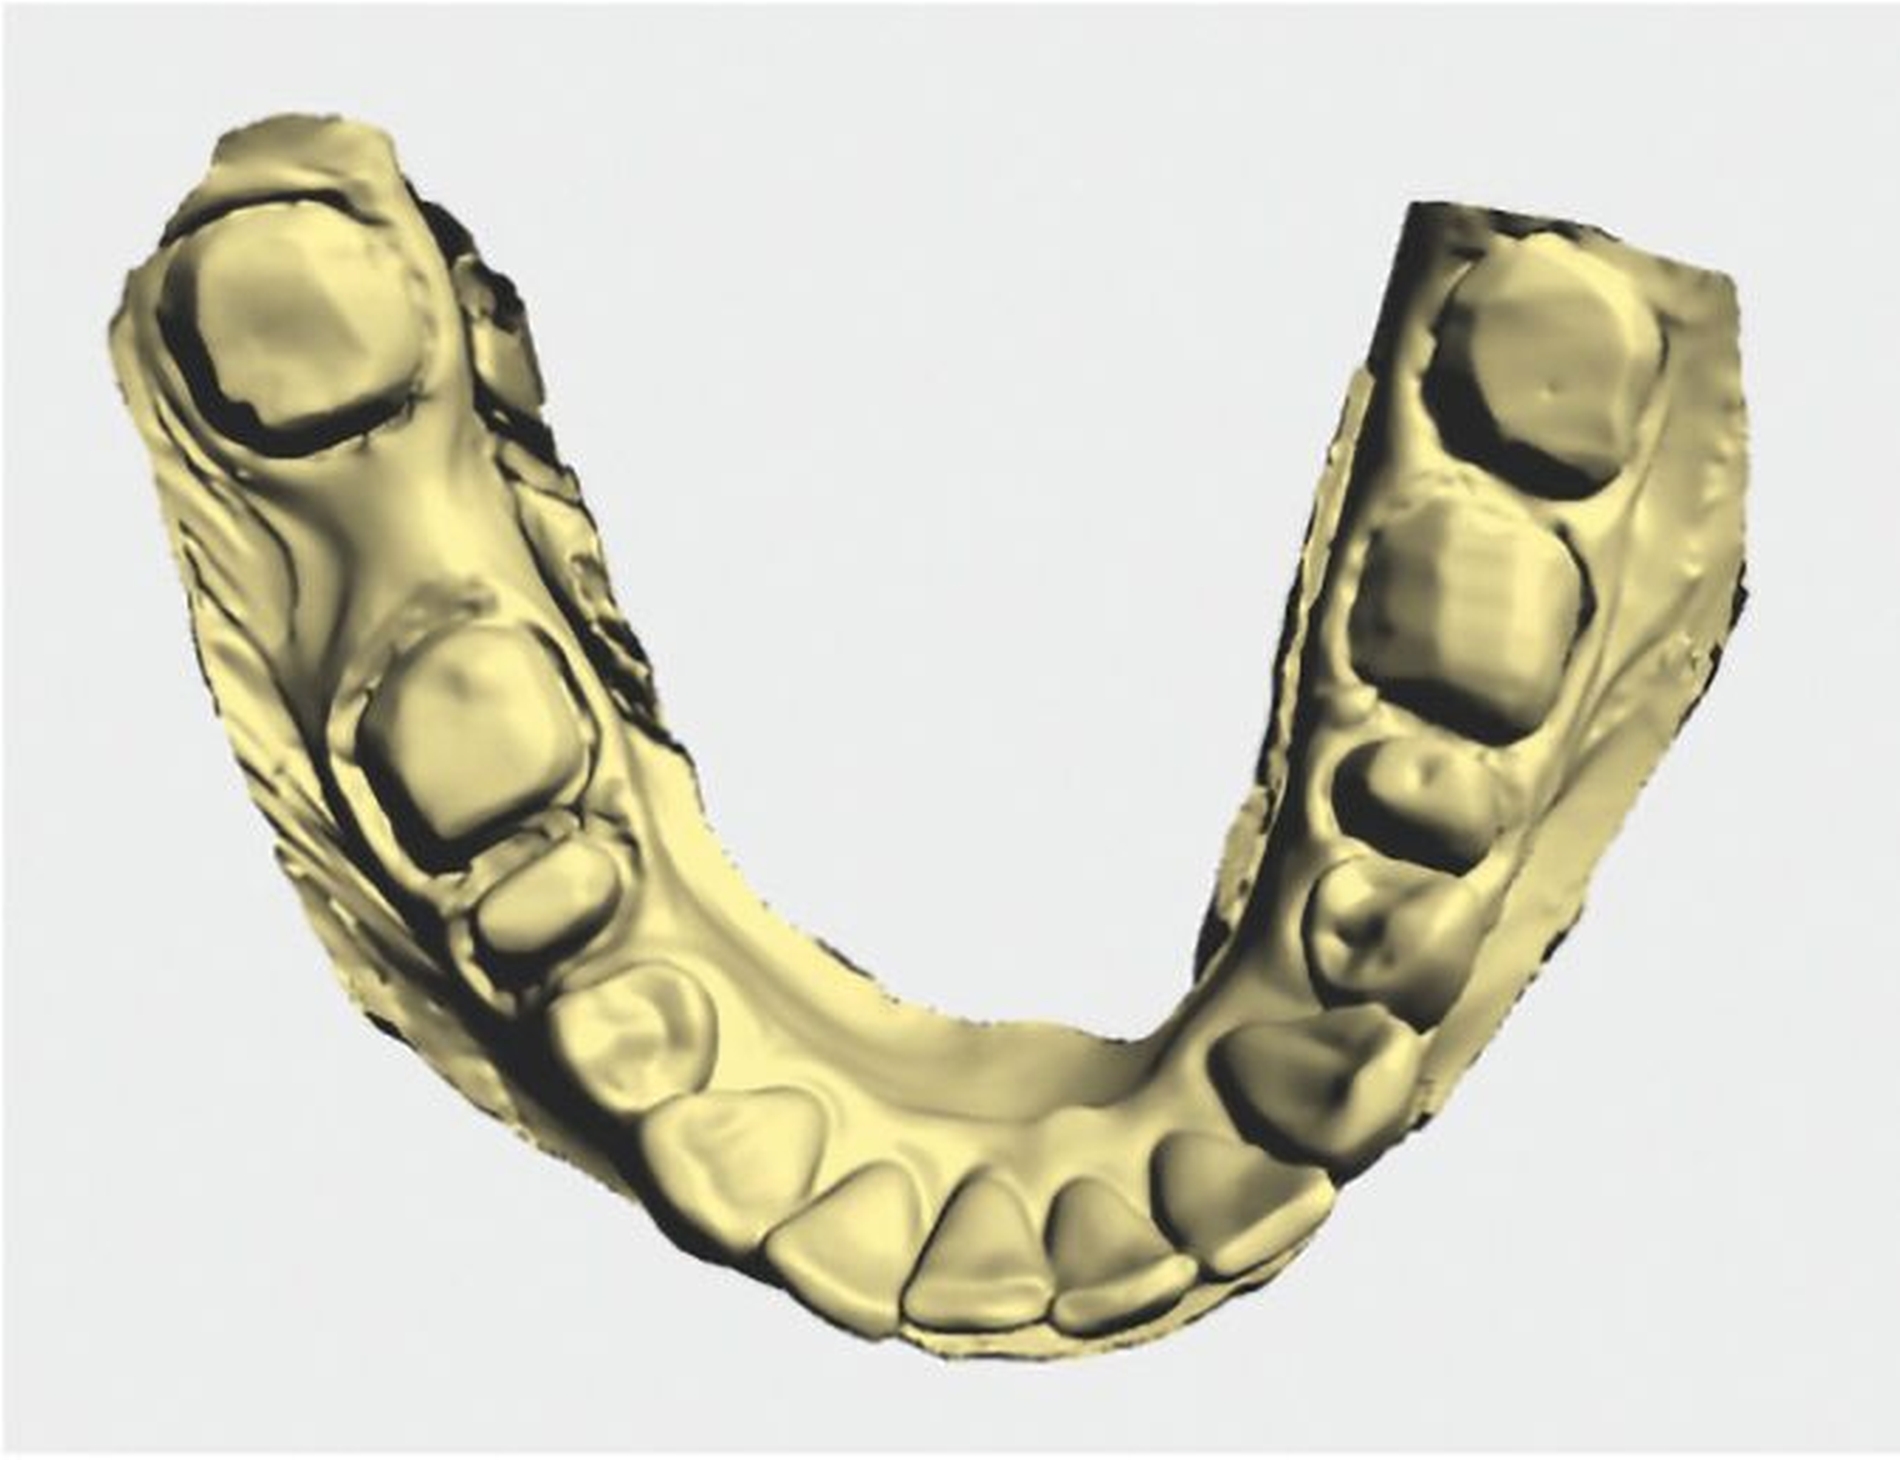

Im zahntechnischen Labor wurde nun im Artikulator mithilfe eines diagnostischen Wax-ups die optimale Okklusion simuliert und analysiert, wie viel fehlende Zahnhartsubstanz durch den Zahnersatz kompensiert werden muss (Abbildungen 6a bis 6e). Letztlich wurde das definitive Therapiekonzepts festgelegt:

im Oberkiefer 15 Kronen (18–27)

im Unterkiefer vier Kronen (35–37 + 45) sowie eine Brücke (48-b-46)

Im Seitenzahnbereich wurden Kronen aus monolithischer Zirkondioxidkeramik und in der Front aus monolithischer Lithiumdisilikatkeramik geplant. Differenzialtherapeutisch wären bei kerngesunden Zähnen Table Tops beziehungsweise Veneers ebenso eine sehr sinnvolle alternative Therapieoption. Diese Möglichkeit schied allerdings aus: Angesichts der tiefen Füllungen und endodontischen Behandlungen waren zahnärztliche Kronen medizinisch indiziert. Die Situationsmodelle mit Wax-up wurden im Verlauf doubliert und Tiefziehschienen erstellt, um die Provisorien nach der Präparation in der neu definierten Kieferrelation herstellen zu können.